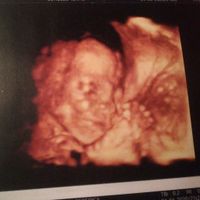

1759 giorni faCiao a tutte! Apro questo sondaggio un po' per gioco un pochino per aiutarmi con il nome del mio prossimo bimbo!💙 Ho un bimbo di quasi 2 anni di nome Daniel. Con lui siamo andati a colpo sicuro con il nome.. sapevamo già che quello sarebbe stato! Ora...